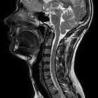

Gehirn, Rückenmark, Nerven